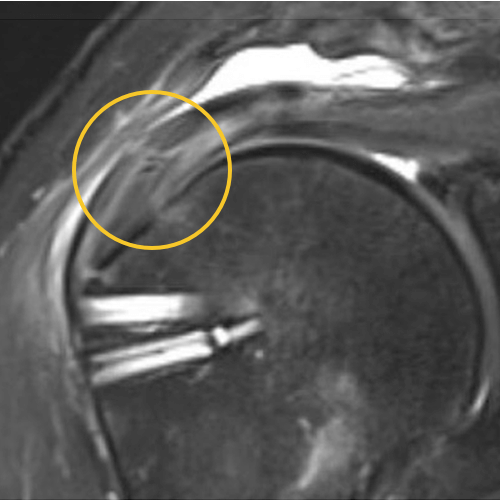

We published this case study in the JOEI (Journal of Orthopedic Experience and Innovation) Journal. We did a revision of the large type-II repair and augmented it with BioBrace®. You can see the pre-op and three-month MRI below. Still fluid in the subacromial space but that tendon is clearly coming across into the footprint. Then, an eight-month MRI shows there's no further fluid in the subacromial space and maturation of that repair across the footprint.

3 Months

8 Months